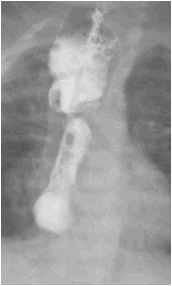

图 4 吻合口漏消失,出现吻合口狭窄

10-19 造影检查: 上消化道造影 (数字化摄影):食道闭锁术后改变,吻合口狭窄。食管裂孔疝;肺炎;近日患儿出现口水增多,考虑和食管狭窄有关,向家长告知病情,建议食管扩张,家长同意,故 2021.10.22 日在全麻下行经口球囊食管扩张术

入院诊断:入院后完善术前检查,给予箱内吸氧(3L/min),头孢他啶抗感染,维生素 K1 预防维生素 K 缺乏性出血,禁饮食、胃肠减压、补液等对症支持治疗。监测血压、血糖、心电、血氧。确诊食管闭锁。于 2021 年 8 月 19 日行经胸膜外食管吻合术,术后出现吻合口漏,感染指标上升。2021.09.05 根据引流液培养缓症链球菌,药敏结果选用头孢哌酮舒巴坦及万福霉素抗感染治疗,感染指标有所下降,但一直未正常,反复出现喂养不耐受,贫血等症状。先后多次因贫血输红悬液治疗。09.14 停用万古霉素抗感染。2021.09.24,取痰培养,2021.09.25 经验升级抗菌素为美罗培南抗感染。09.26 日行 mNGS 检测。09.27mNGS 结果回报提示为粘质沙雷氏菌,大肠埃希菌,缓症链球菌,产气克雷伯氏菌。同时痰培养结果回报。痰培养结果提示未大肠埃希菌但是几乎全部耐药,仅替加环素敏感。同时提示还有 CMV 感染。考虑多重感染可能性大,继续应用对粘质沙雷氏菌,大肠埃希菌,缓症链球菌,产气克雷伯氏菌等病原均有作用的美罗培南抗感染,同时停用对耳肾毒性较大的万古霉素抗感染。患儿精神状况好转,感染指标逐渐下降至正常,喂养耐受,肠内营养增加,贫血改善。2021.10.09 血常规及 c 反应蛋白正常,感染控制。2021.10.19 复查造影提示吻合口漏愈合(图 4)。10 月 22 日因食管狭窄再次行食管狭窄扩张治疗,术后恢复顺利,10.28 达到临床治愈出院。